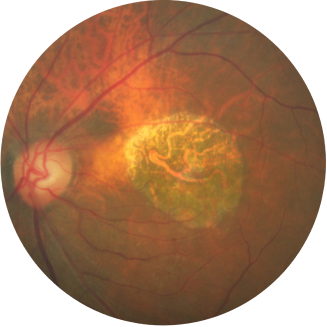

Retinografia de um olho com atrofia geográfica

O crescimento da lesão pode levar ao declínio visual.1,12,13

A acuidade visual não se correlaciona fortemente com o crescimento da lesão de atrofia geográfica. A visão funcional diminui à medida que as lesões crescem.14

Avaliação inicial Ano 1

BCVA 20/63+, área de AG de 5,18 mm2

Avaliação inicial Ano 2

BCVA 20/80-2, área de AG de 10,39 mm2

Avaliação inicial Ano 5

BCVA 20/200, área de AG de 18,58 mm2

As imagens são cortesia do Dr. David Elchenbaum, da Retina Vitreous Associates of Florida.

BCVA = melhor acuidade visual corrigida (best corrected visual acuity).